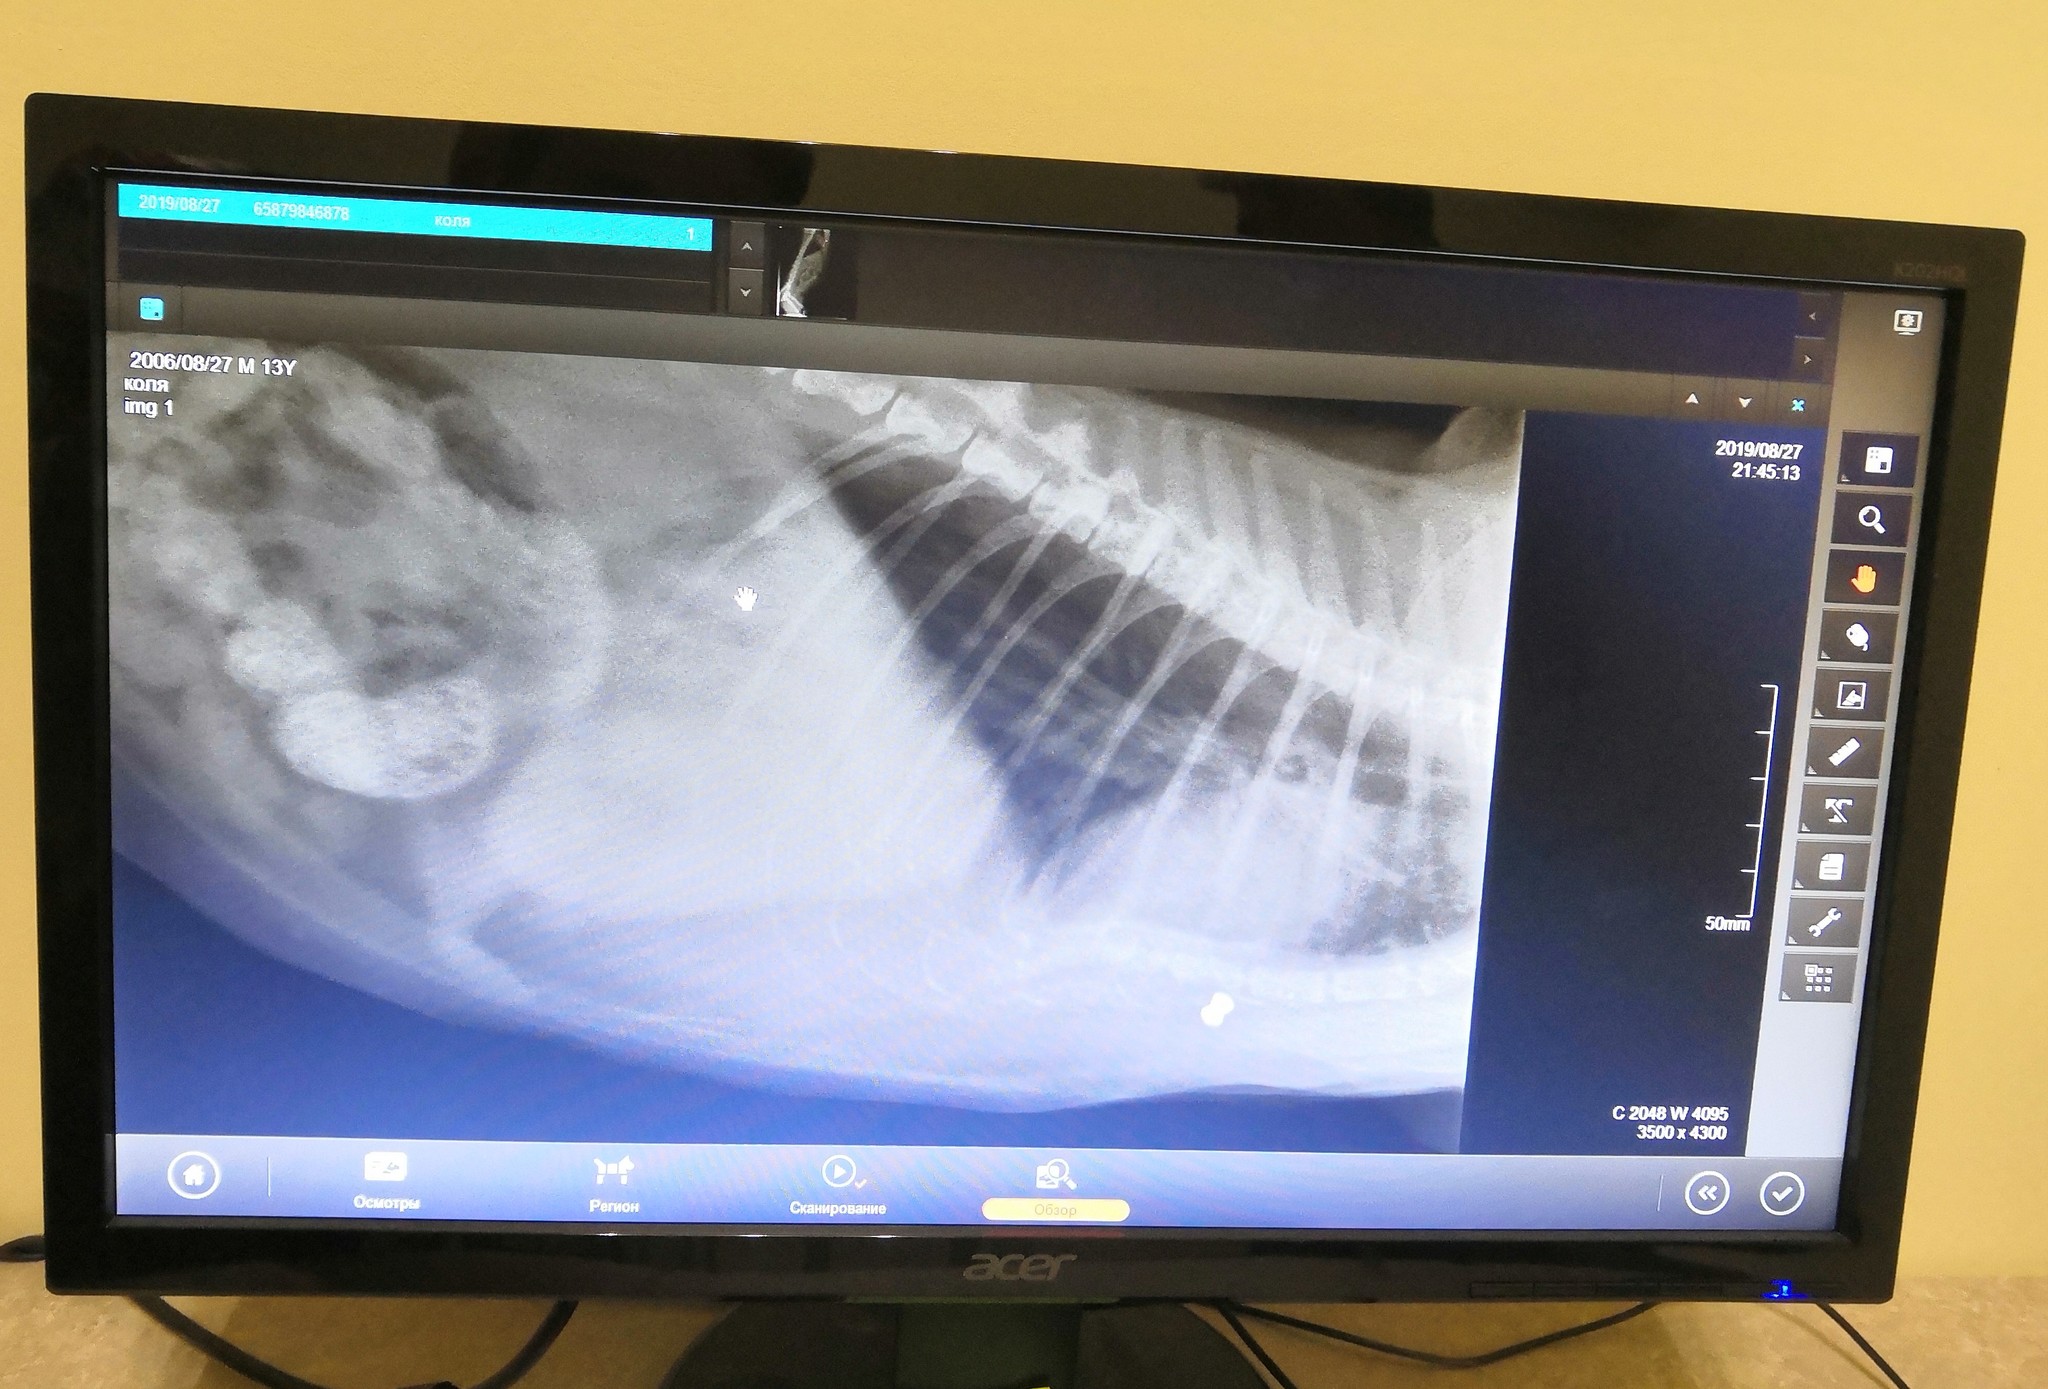

Ради интереса и полноты картины решили сделать рентген

Я замер, сердце начало дубасить, я моргал пытаясь развидеть, но не получилось

Маленькая белая точка была подозрительно похожа на пульку воздушки (дед был инструктором по стрельбе).

В добавок к этому, друг показал на старый перелом грудины.

сделали второй снимок

Начали прощупывать, нашли уплотнение от которого кот приходил в бешенство при попытке более тщательно потрогать.

Вердик был краток: Было, зажило, сейчас ничего не нужно кроме диеты. Пулька снаружи грудной, с этим живут и не переживают. Приходи через месяц посмотрим что будет.